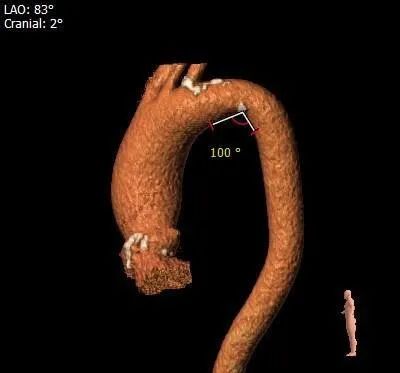

主动脉弓测量: